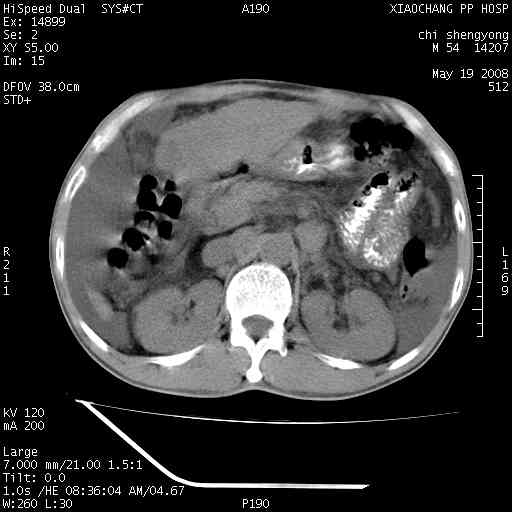

以下是引用zjzjr在2008-5-21 10:52:00的发言:[br]肝左叶巨块型肝癌伴门静脉左支瘤栓形成.肝硬化、腹水,胃底静脉曲张,脾术后改变。

以下是引用随光逐影在2008-5-21 16:20:00的发言:[br]1)肝左叶肝癌伴门静脉左支瘤栓形成,腹膜后淋巴结转移。2)肝硬化、腹水、胃底静脉曲张。3)胆囊炎。4)脾脏缺如,为切除术后所致。